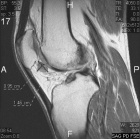

29 year old male c/o right knee pain x six months. No trauma.

Zoom image: Radiological image Radiological image.